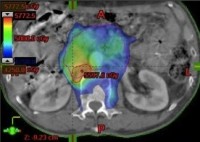

Intensity Modulated Radiotherapy (IMRT) and

Image Guided Radiotherapy (IGRT)

IGRT and IMRT are very significant advances in the field of external beam radiation therapy. Developed and refined over the past several years, they have now become much more widely adopted by radiation oncologists nationally and internationally. Standard radiation in the modern era is called '3D conformal radiation'. With 3D treatment, multiple beams are used and shaped to optimally treat a tumor while sparing normal tissue. However IMRT represents an advance because the amount of radiation delivered across any particular beam can vary. This is achieved by rapidly sliding 'multileaf collimators' which enter and exit the beam quickly, changing the characteristics of the beam profile. Combined with multiple radiation fields, it offers more flexibility in treating tumors and protecting normal organs. IGRT refers to image guided radiation therapy. With IGRT, tumor localization is used which gives instant feedback to the radiation therapy team and allows for refinement of patient positioning. For example, some modern linear accelerators use an on-board CT scanner, others use diagnostic x-rays combined with implantable gold markers (called fiducials). Calypso (described above) is a type of IGRT. IGRT and IMRT represent a significant advance in many cases but are not always indicated or advantageous. Your physician can help explain the details of treatment delivery and the best techology available. TIROG is a leader in IGRT and IMRT technologies. We teach regular IGRT educational courses which are attending by radiation oncologists worldwide. IMRT and IGRT are now available at all of the radiation treatment locations where TIROG physicians practice.